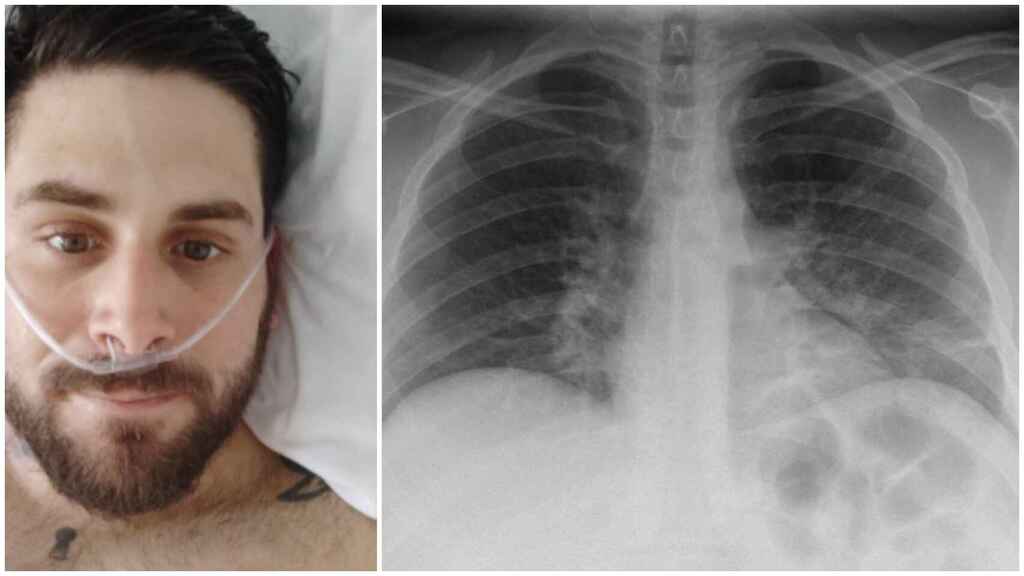

México.-Los órganos más dañados de los pacientes que se recuperan de Covid-19 son los pulmones, es por ello que la UNAM impartirá talleres de rehabilitación para que las personas que han tenido coronavirus, puedan mejorar su respiración.